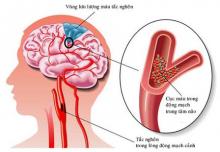

Dị dạng động-tĩnh mạch não (AVM) là những tổn thương mạch máu hiếm gặp có thể biểu hiện bằng xuất huyết nội sọ tự phát, co giật hoặc đau đầu, điển hình ở người trẻ tuổi.

Xuất huyết do AVM não thường là trong nhu mô nhưng có thể dưới nhện hoặc trong não thất.

Đối với dị dạng động mạch não, mục tiêu chính của điều trị là ngăn ngừa đột quỵ chảy máu não. Rủi ro của các phương pháp điều trị khác nhau phải được cân nhắc với những rủi ro trong bệnh sử tự nhiên của AVM .